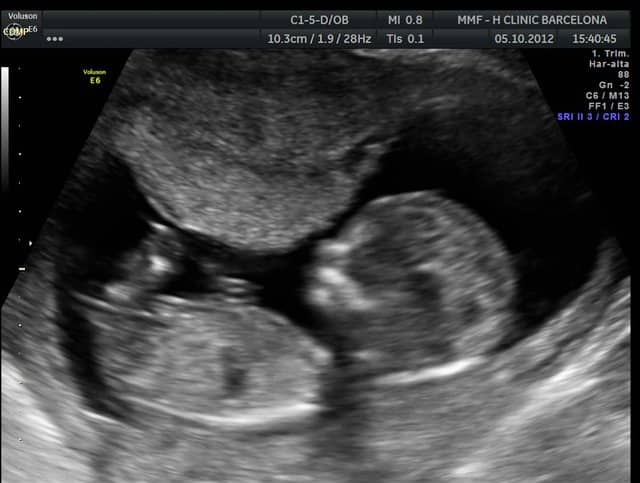

Ecografia 2d De La Semana 12 Cuanto Mide El Feto Natalben

Ecografia Semana 12 De Gestacion 12 Weeks Gestation Sonography Youtube

Ecografia De La Semana 12 Como Se Mide Al Feto Natalben

Semana 12 De Embarazo La Ecografia De Las 12 Semanas